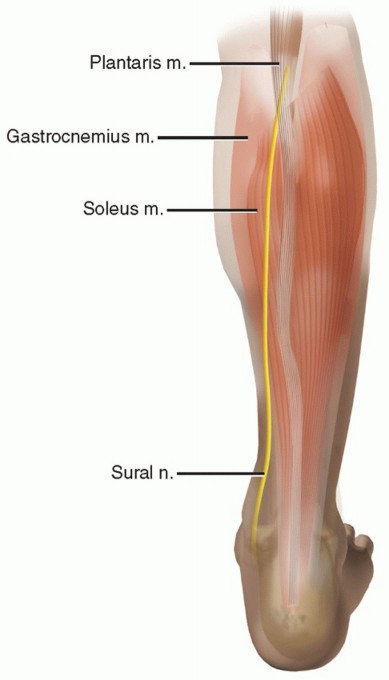

DEFINITION Achilles tendon ruptures typically occur about 2 to 6 cm proximal to the tendon's insertion site o…